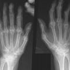

RA is a chronic inflammation of the joints caused when the body’s immune system destroys its own tissue, unlike osteoarthritis, which is caused by external damage to joints and connective tissue. Throughout the world, RA is generally more common in women than in men, which suggests that hormones may be playing a part. This is borne out by the fact that it usually goes into remission during pregnancy, and is very unusual for the disease to begin at that time. However, in the few weeks after delivery, women with RA often experience a relapse and there is a much higher frequency of development of RA. This may be because prolactin, the hormone which is responsible for milk production, enhances inflammation which is a key factor in RA.